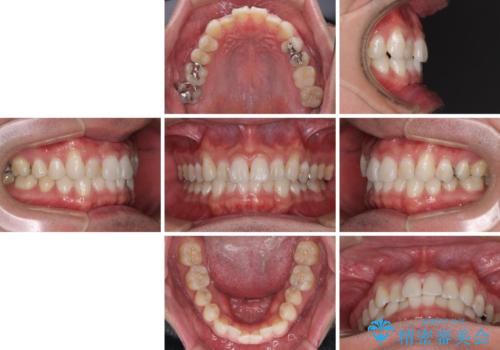

【モニター】 インビザライン・ライトによる軽微叢生の矯正治療

- 30代男性

- インビザライン・ライト

- 4ヶ月

- 2-5回

- 上下前歯の叢生を気にして来院された患者様です。

費用を抑え、期間もあまりかけずに治療をしたいとのことで、インビザライン・ライトを用いて矯正治療を行うこととしました。

- 治療費の目安: 45万円(税込)費用は治療当時の料金となります